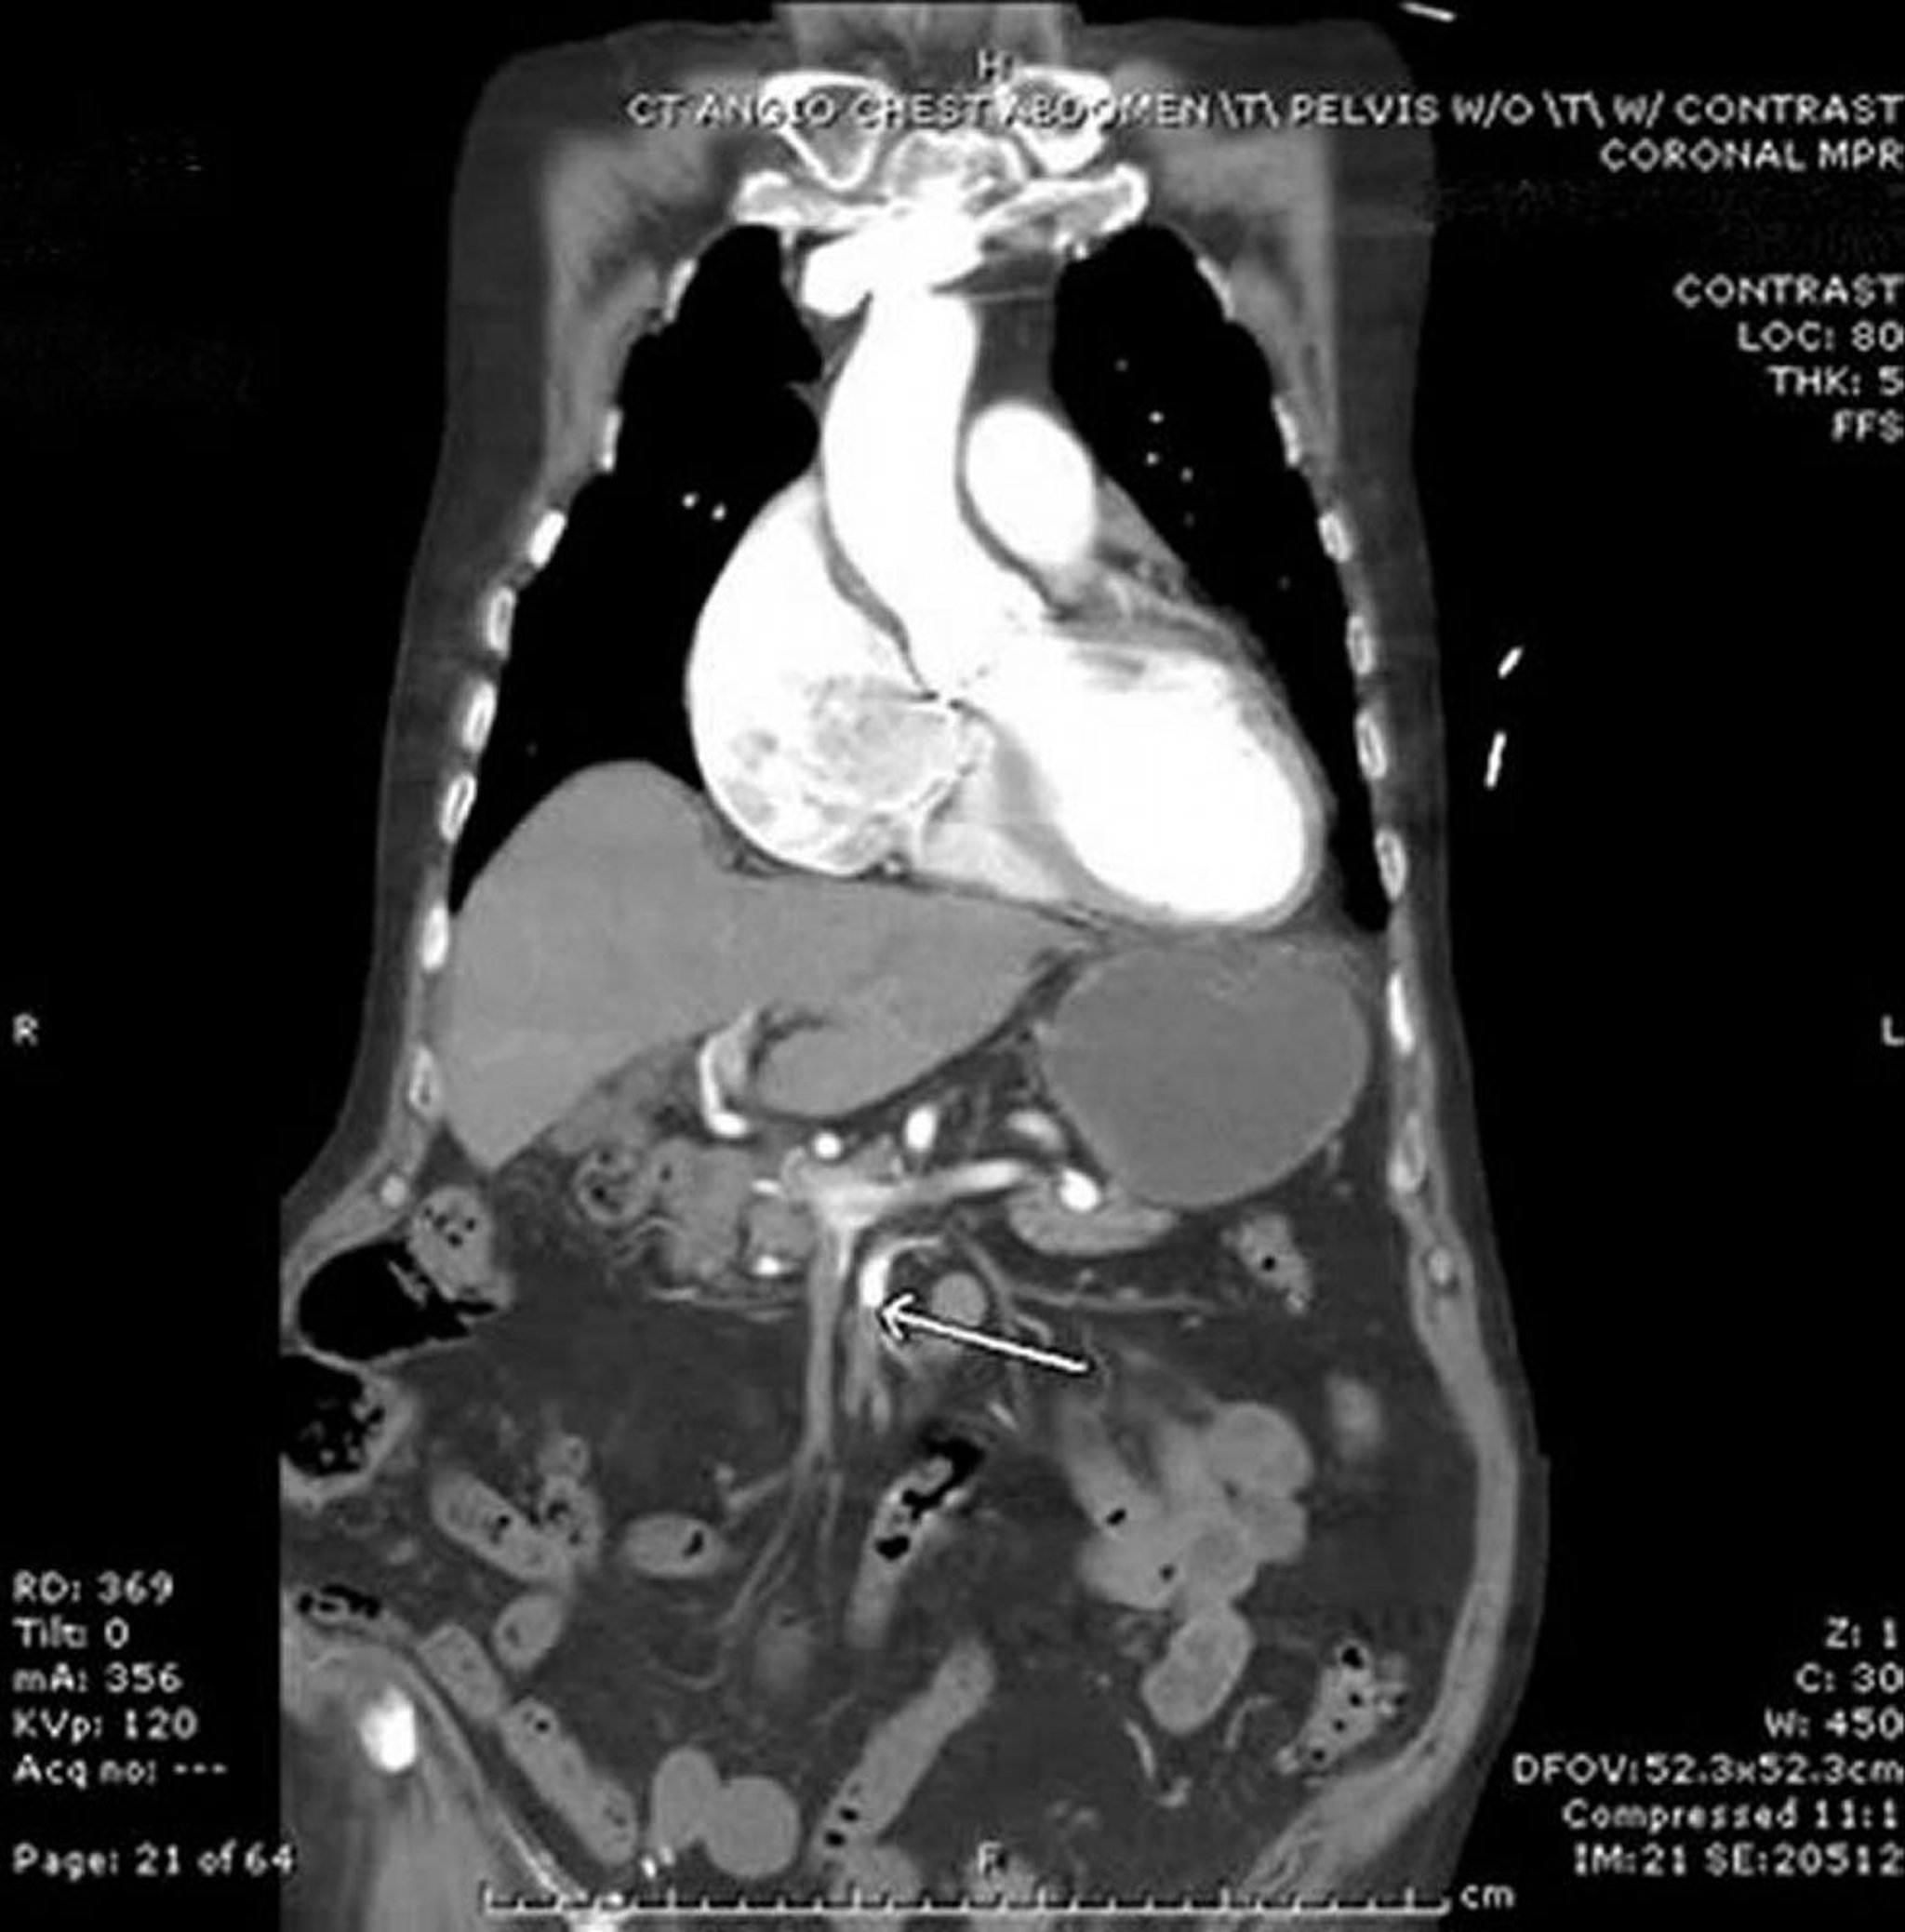

Isquemia mesentérica (angiografía por TC)

En esta imagen, la flecha señala la arteria mesentérica superior, que muestra una interrupción brusca del contraste intravenoso. Se observa algo de engrosamiento del intestino delgado en el hemiabdomen izquierdo. Este caso de embolia proviene del corazón en un paciente con fibrilación auricular.

Image provided by Parswa Ansari, MD.